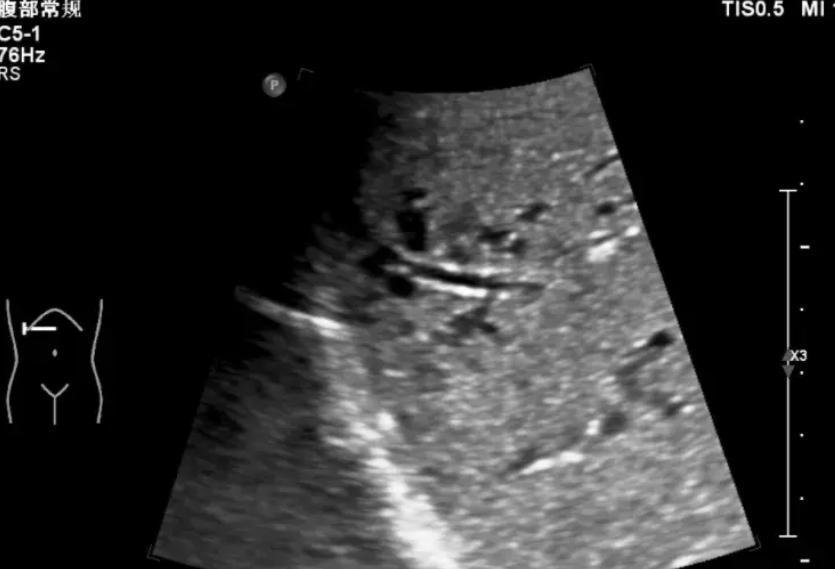

一旦多个表现“对上号”,就别再自己买药“消肿、活血”了,先去正规医院做个血常规、肝功能、肾功能、尿常规、腹部B超,比盲目拖延强得多。

建议40岁以后,每年至少做一次肝功能、肾功能、腹部超声,有肝炎、糖尿病、高血压家族史的人,更要提前重视。脚上的变化,常常是全身问题的“窗口”。